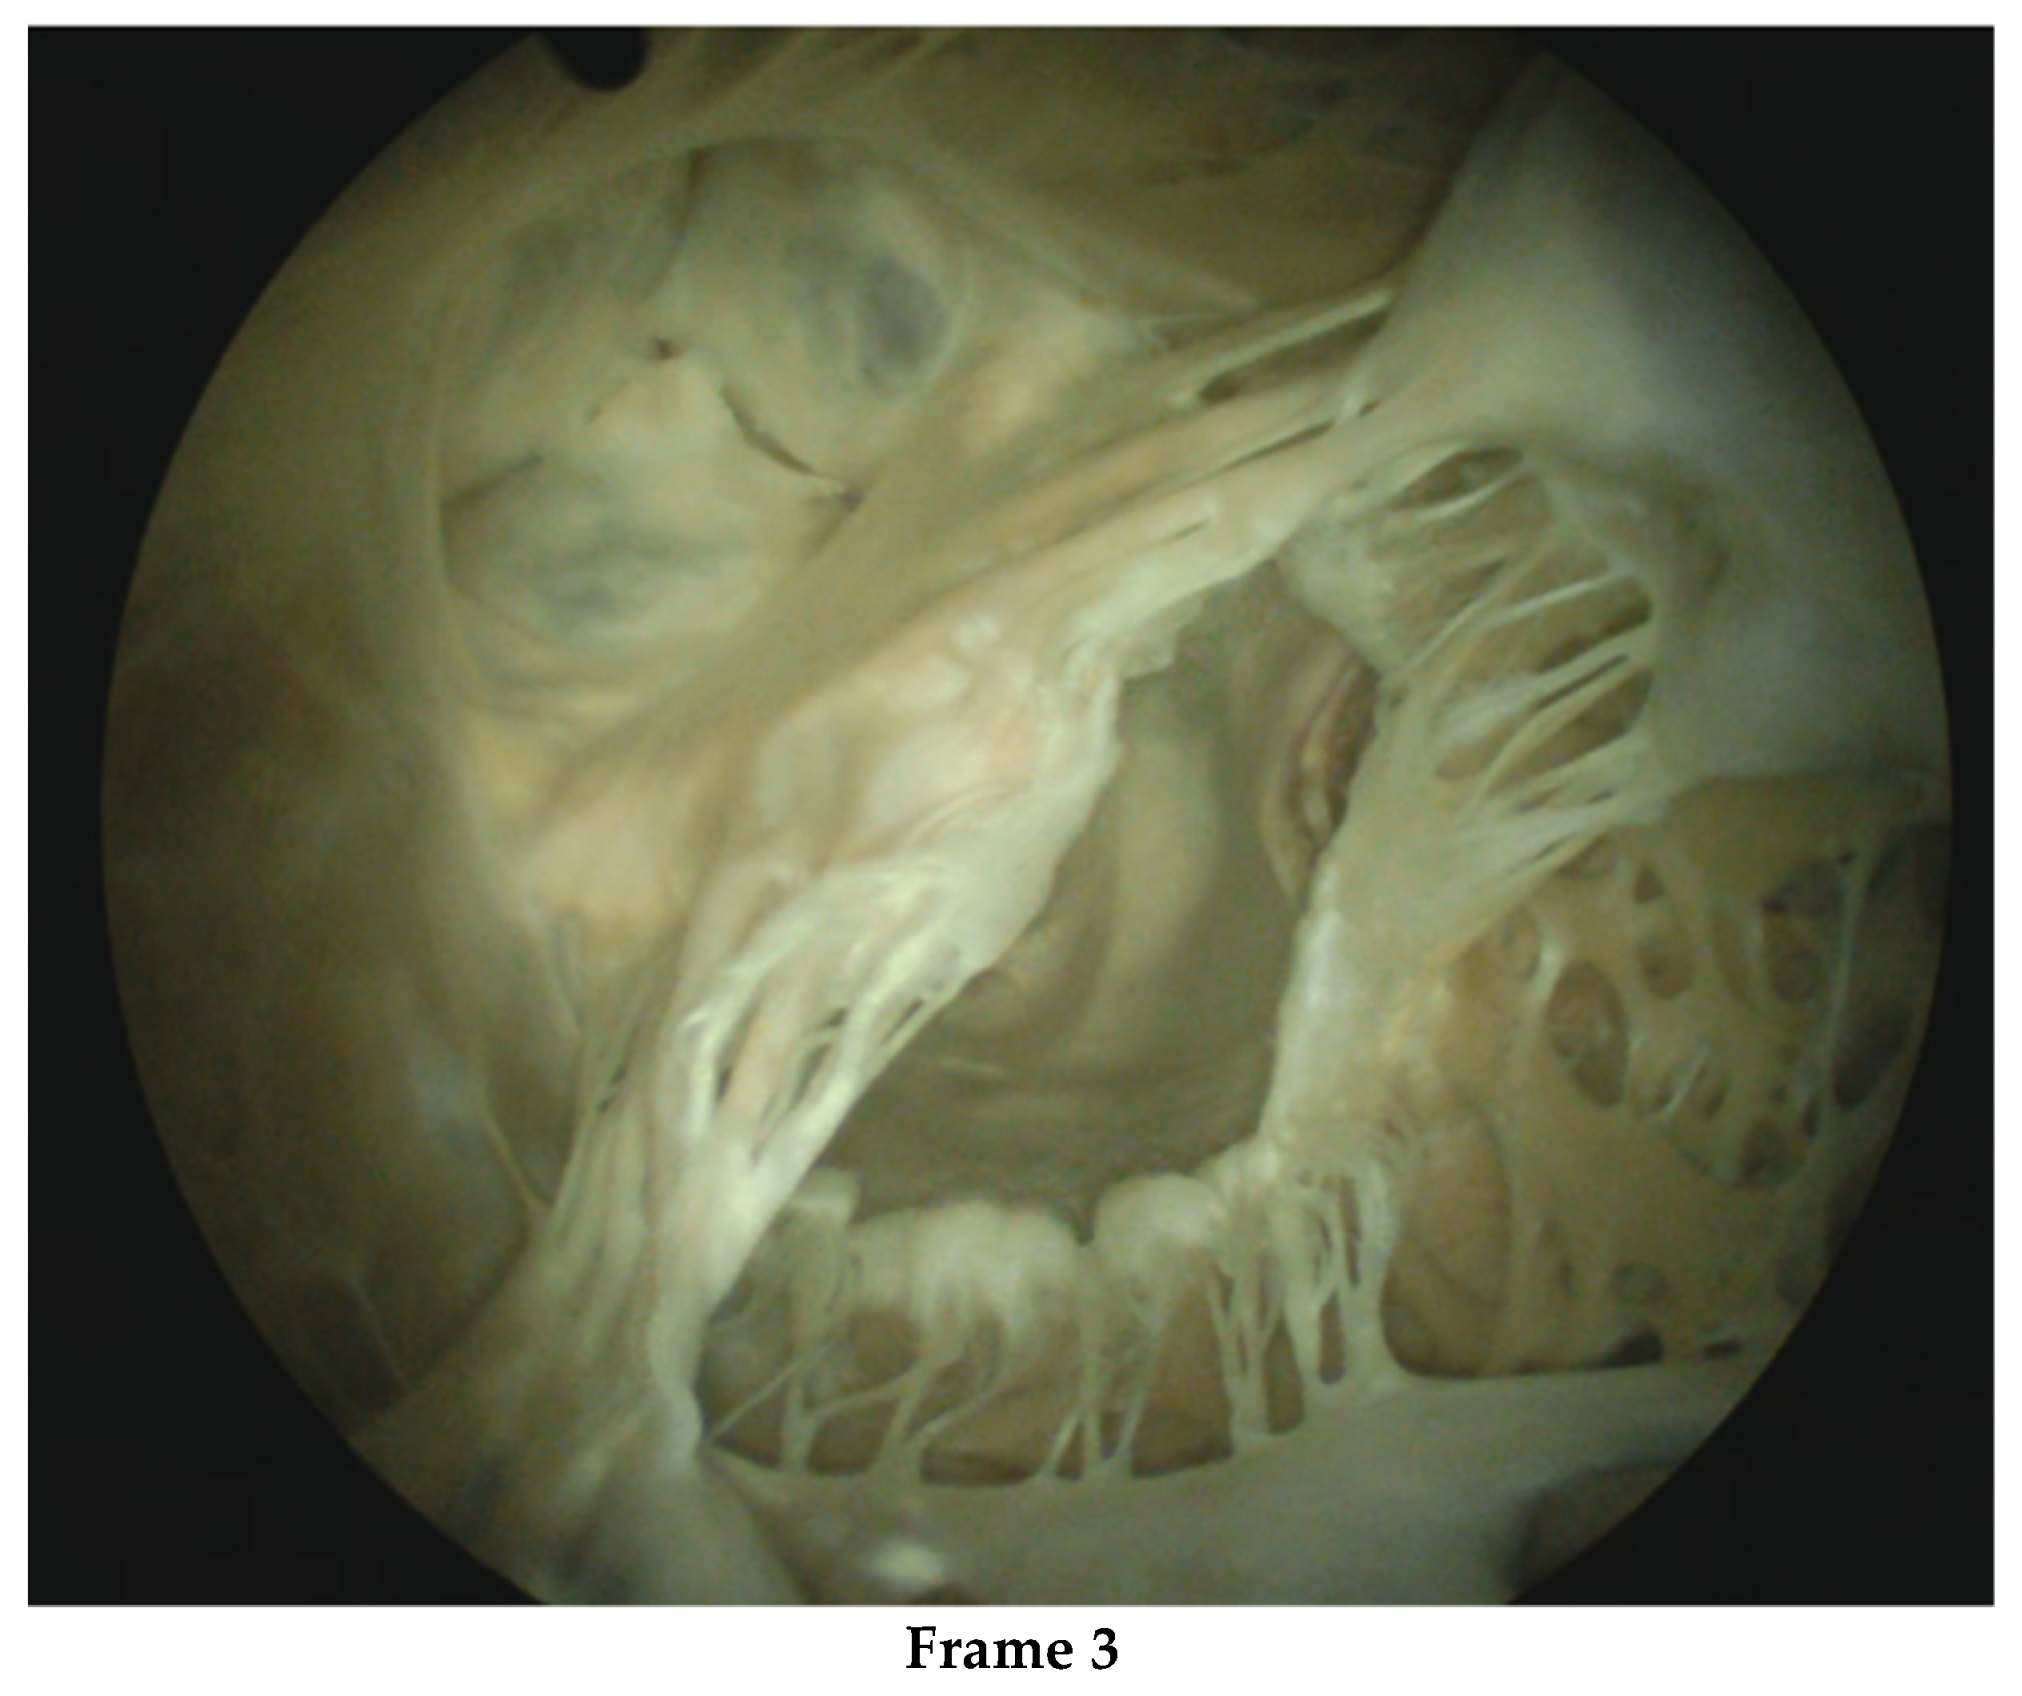

The aforementioned imaging add-ons may simplify surgical duties and tasks despite their technical complexity, but these require specialized knowledge and computer competence. Computer/ robotic assistance also forces surgeons to reflect on the boundaries of their surgical proficiency and skill building. Control of the surgical surroundings has become far more complex than the operation itself. The proficiency of the surgical team and the institution should be critically examined. From admission to rehabilitation care, within a surgical group and the institution, minimal invasiveness must be the common interventional approach supported by adequate infrastructure, cost-effective logistics and educated and skilled workers. Surgeons are not infallible and, in our experience, some cases of bleeding and death were associated with suboptimal surgical performance. It remains a challenge to select surgeons for MIMVS and to train them effectively. Apart from learning-by-doing, simulators may be used to select candidates for MIMVS and accelerate proficiency, especially if human cadaver hearts are used [75,76,77]. See Figure 2.

Figure 2.

After thawing, the human cadaver heart is embalmed with a specialized solution of a very low toxicity. This embalmment ensures preservation, safe and user-friendly handling of the heart and tools and improves tissue quality, which allows for physiologic load of the heart, although protection measures always remain in place. Frame 1. provides an external view of the embalmed human cadaver heart. Frame 2. shows a TEE of the pulsating heart with an assessment of the diameter of the mitral valve diameter, the association with the aortic valve and length of chordae. Frame 3. presents a still of the videoscopic presentation of the left ventricle and partial left atrium.

Beating human cadaver hearts with intact arterial and venous connections provide an excellent real-life training platform. In prescreening, the human cadaver heart can be inspected and tested, to ensure that the heart is suitable for the test or teaching requirements. Such a platform can be placed in a cath-lab imaging environment including 3-D echocardiography. The setting is not only effective for testing devices, but also for assessing how much imaging information and device handling a trained operator can safely master. The platform may reveal complex usability issues relevant to organizing the work processes and safe learning of MIMVS by junior surgeons and to mastering new technology by advanced surgeons. Safe and fast MIMVS starts with excellent surgeons, and in our opinion technical innovation is no substitute for suboptimal surgical skills. In contrast, high-tech support for moderately competent surgeons may create serious additional risks, including the interruption of workflow [78].